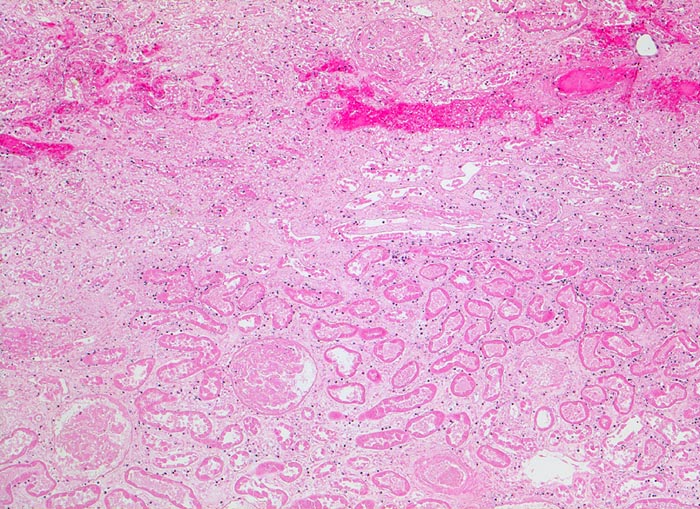

PathoPic – image database / PathoPic ID 4867 - akuter Niereninfarkt mit hämorrhagischem Randsaum

akuter Niereninfarkt mit hämorrhagischem Randsaum

vaskulär / Durchblutungsstörung

Niere

Ausschnitt aus dem Randbereich der Koagulationsnekrose mit hämorrhagischem Randsaum (oben)

Chronisches Vorhofflimmern mit Morbus embolicus: anämische Infarkte verschiedenen Alters in beiden Nieren und in der Milz. Alte abgebaute Enzephalomalazie im Versorgungsbereich der Arteria cerebri media rechts.

Histologie

50